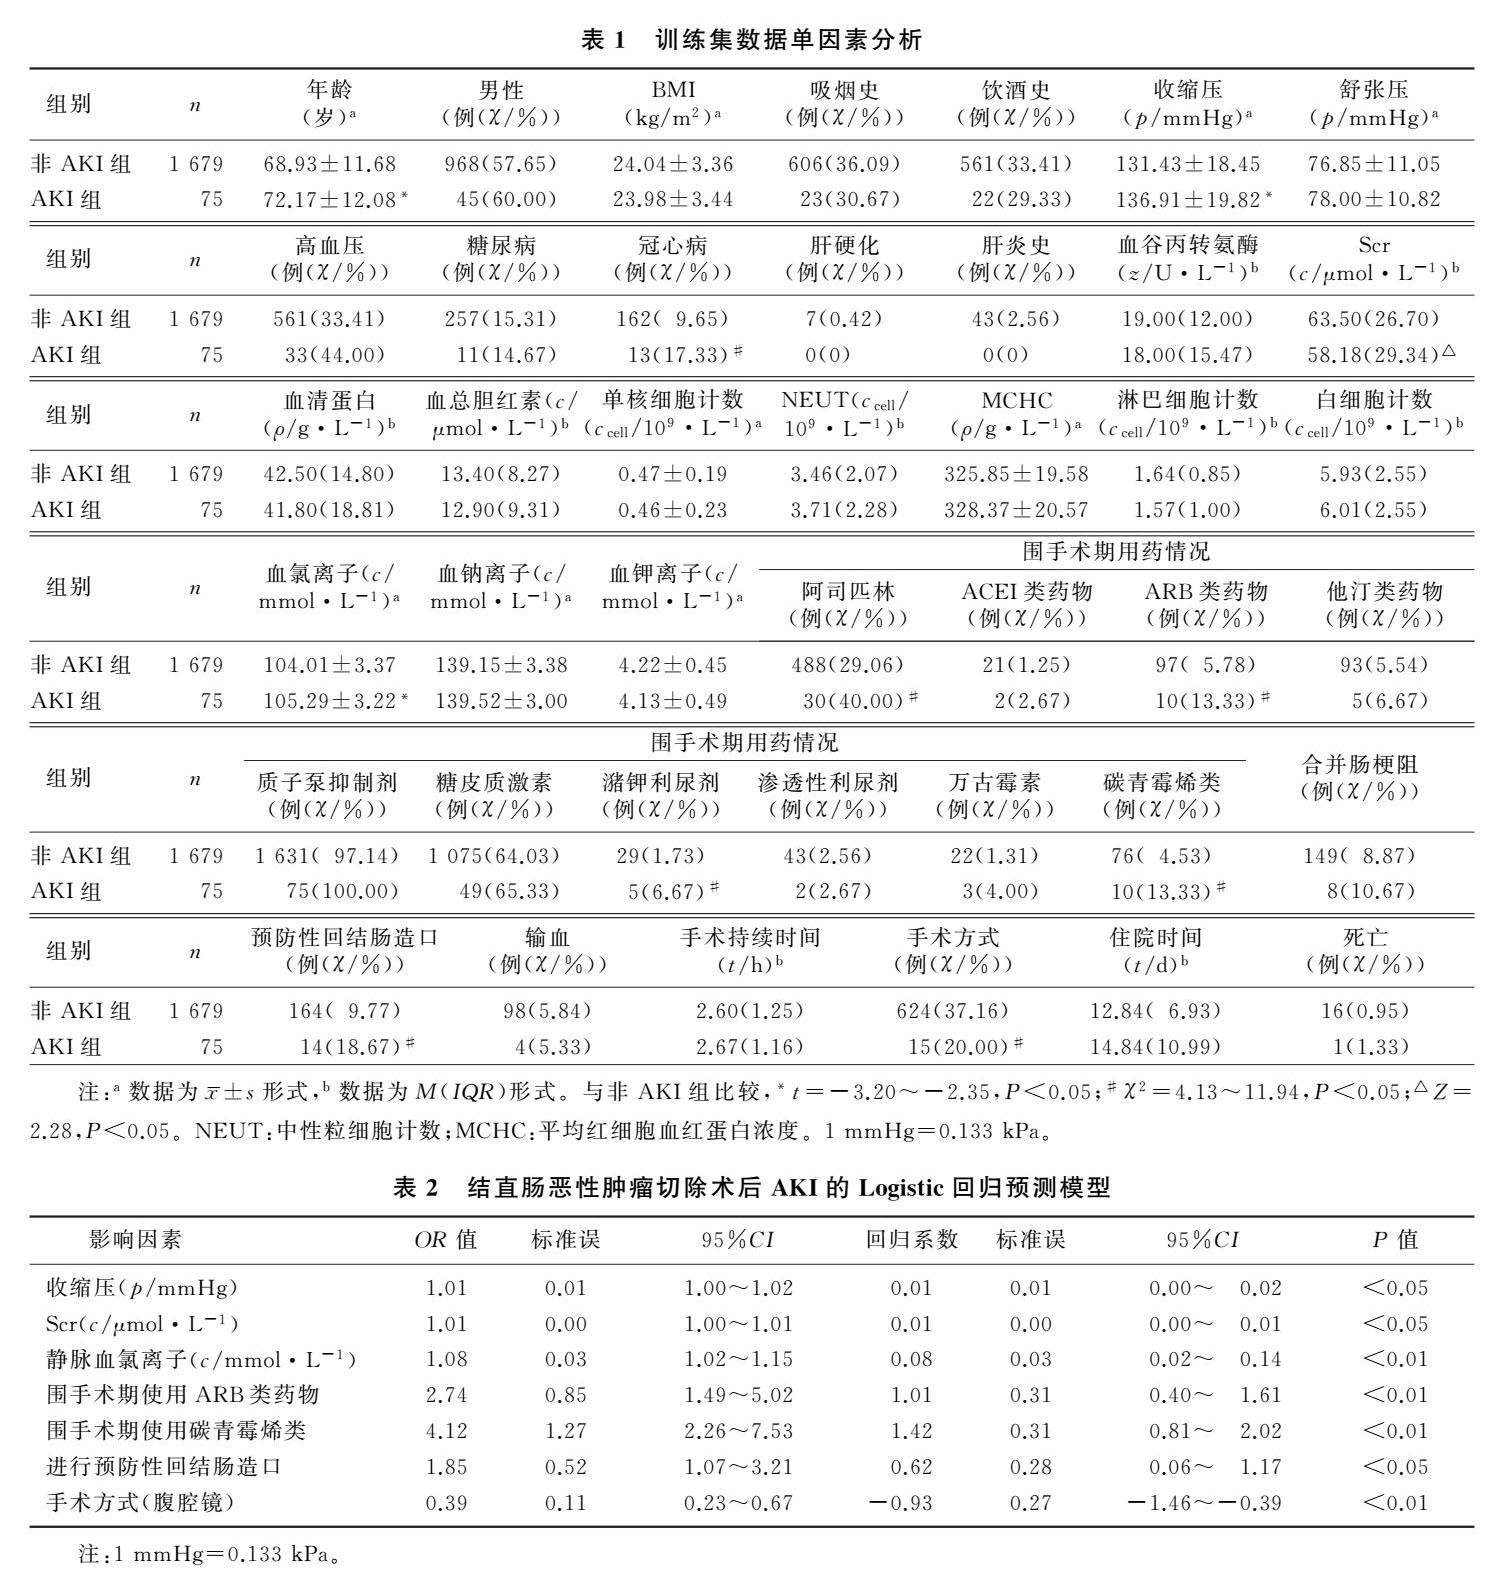

论著 | 结直肠恶性肿瘤切除术继发急性肾损伤的危险因素及预测模型

论著 | 结直肠恶性肿瘤切除术继发急性肾损伤的危险因素及预测模型